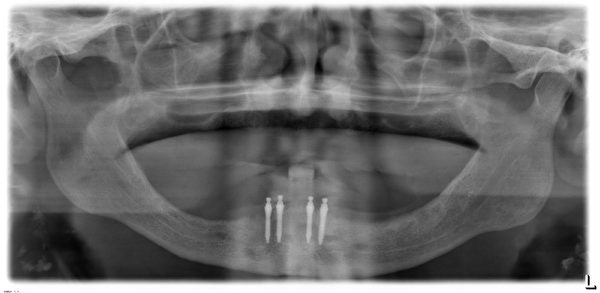

什么是MINI种植体

Mini种植体是一种直径比常规种植体小很多的特殊植体,它是用于活动义齿的修复中,要比传统的义齿修复更加稳定。

Mini种植体允许牙医不用在牙龈上切口直接植入,术后手术痛苦减少,且可以进行即刻修复

目前新加坡有两种植牙技术,一种是迷你植牙,用细小的螺丝来固定牙齿,直径只有约两毫米。

相反的,迷你植牙只需几天,价格是传统植牙的一半。

迷你植牙,它是一种伤口小的微创手术。一些80岁以上的病人,不适合做传统植牙,因为骨头厚度不够,但可利用迷你植牙,帮他们植牙,改变他们的生活。

不过迷你植牙金属较薄,支撑度没有比传统植牙的金属强,长期用力可能破裂。